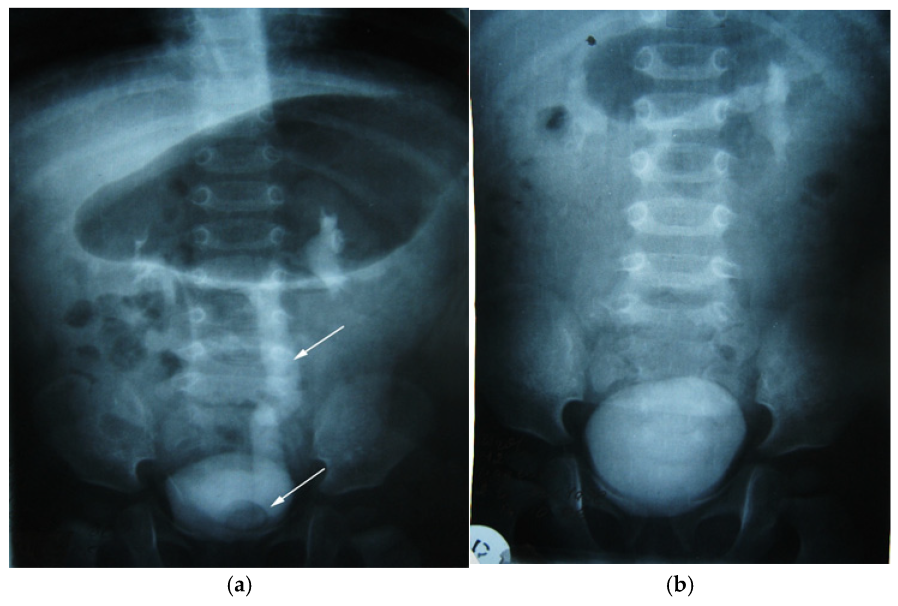

Figure 10. Intravenous urography. Orthotopic left ureterocele, preoperative (a) and postoperative after 2 years (b). Top arrow—ureter dilated up. Lower arrow—orthotopic ureterocele (simple).

We present another clinical case of a 1-year-old child with an antenatal diagnosis of left hydronephrosis, established at 20 weeks of gestation. Natural birth at 39 weeks, with a circular umbilical cord, birth weight 3310 g. The patient had no symptomatology until one year after birth; the only clinical sign was two-stage emptying of the bladder. The clinical symptoms were that of a reno-urinary condition, to which fever, nausea, vomiting, and abdominal pain were added. Laboratory tests have consistently revealed hyperleukocytosis and increased ESR (Erythrocyte Sedimentation Rate). Ultrasound of the urinary system was the main exploration, which allowed the diagnosis to be established: pyelectasia and left ureterohydronephrosis, with orthotopic ureterocele (simple) on the left. An in-depth examination, supplemented by intravenous urography, confirmed left ureterohydronephrosis of the left kidney with orthotopic (simple) ureterocele (Figure 10a). The child underwent surgical correction according to the clinical protocol. Orthotopic ureterocele excision was performed histopathologically confirmed on the excised fragment. Ureterocystoneoanastomosis with anti-reflux protection on the left. The child was monitored postoperatively according to a scheme used in the pediatric urology clinic (Figure 10b). The study showed no signs of recurrence. The postoperative evolution was devoid of events, and the clinical and paraclinical examination attests to the perfect functionality of the anastomosis and the absence of any sign of recurrence at the two-year follow-up.